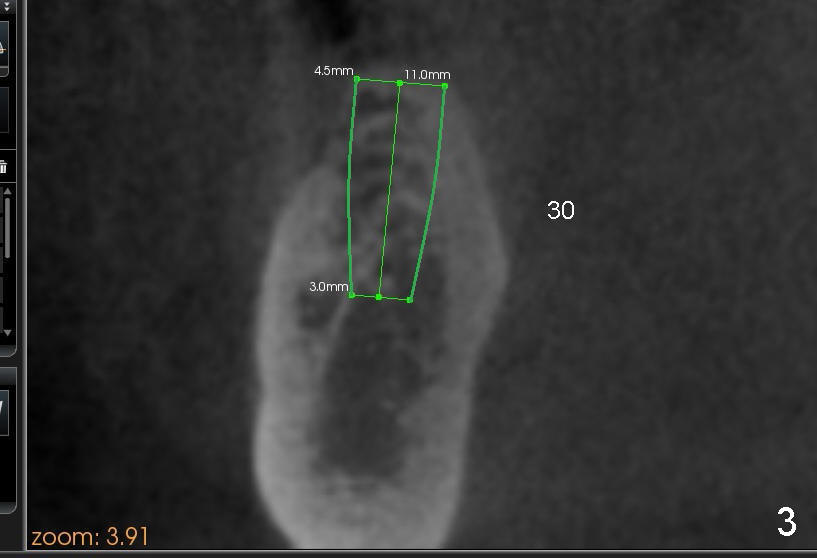

A 56-year-old lady requests implant placement at the sites of #18,30 and 31 (Fig.1, the last two first). CBCT shows preliminary design for implants at #30 and 31 (Fig.2 (sagittal section), 3,4 (coronal)).